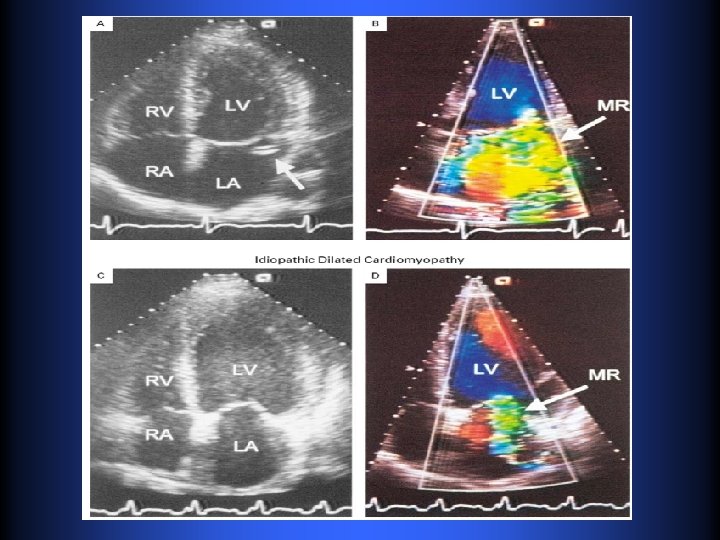

AYUDAS DIAGNÓSTICAS § Ecocardiografía • Evaluación basal de tamaño y Fx VI • Tamaño de AI y VD • Severidad de IM y PAP • Buscar posible etiología de la IM • Seguimiento anual o bianual en IM mod a sev • Si hay cambio de sintomatología • Luego de RVM o reparo • Evaluación con Ej

AYUDAS DIAGNÓSTICAS § Eco cardiografía TE • Establecer base anatómica pre o intra Qx • Información no Dx en el TT • Evaluar posibilidad de reparo si es candidato a cirugía § Seguimiento Eco cardiográfico • IM leve, asintomático, sin alteración en eco • Moderada • Severa